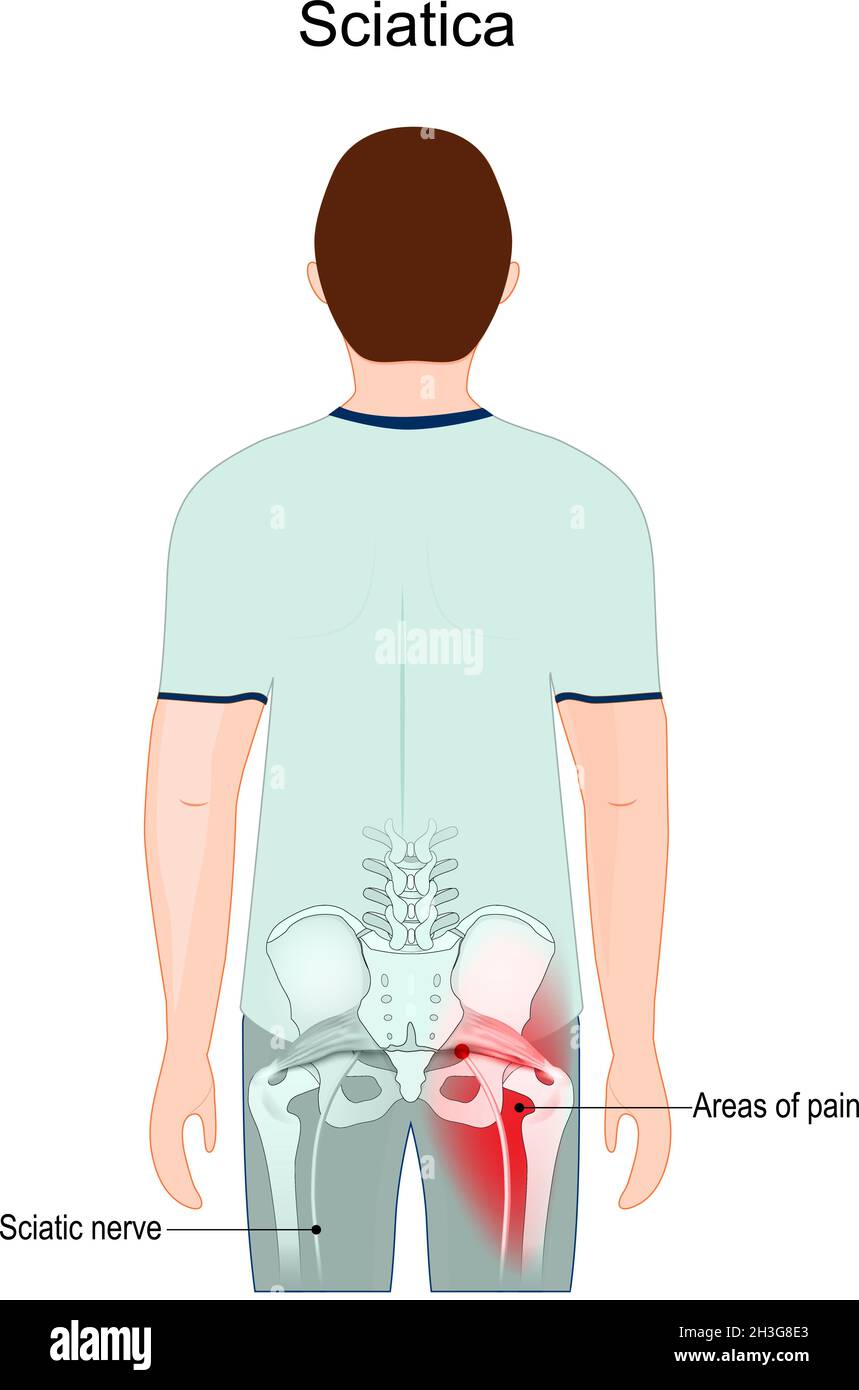

Sciatique.Zones de douleur.Nerf sciatique du bas du dos et de la région de la hanche à travers les hanches à la jambe. Illustration de Vecteurhttps://www.alamyimages.fr/image-license-details/?v=1https://www.alamyimages.fr/sciatique-zones-de-douleur-nerf-sciatique-du-bas-du-dos-et-de-la-region-de-la-hanche-a-travers-les-hanches-a-la-jambe-image449671435.html

Sciatique.Zones de douleur.Nerf sciatique du bas du dos et de la région de la hanche à travers les hanches à la jambe. Illustration de Vecteurhttps://www.alamyimages.fr/image-license-details/?v=1https://www.alamyimages.fr/sciatique-zones-de-douleur-nerf-sciatique-du-bas-du-dos-et-de-la-region-de-la-hanche-a-travers-les-hanches-a-la-jambe-image449671435.htmlRF2H3G8E3–Sciatique.Zones de douleur.Nerf sciatique du bas du dos et de la région de la hanche à travers les hanches à la jambe.